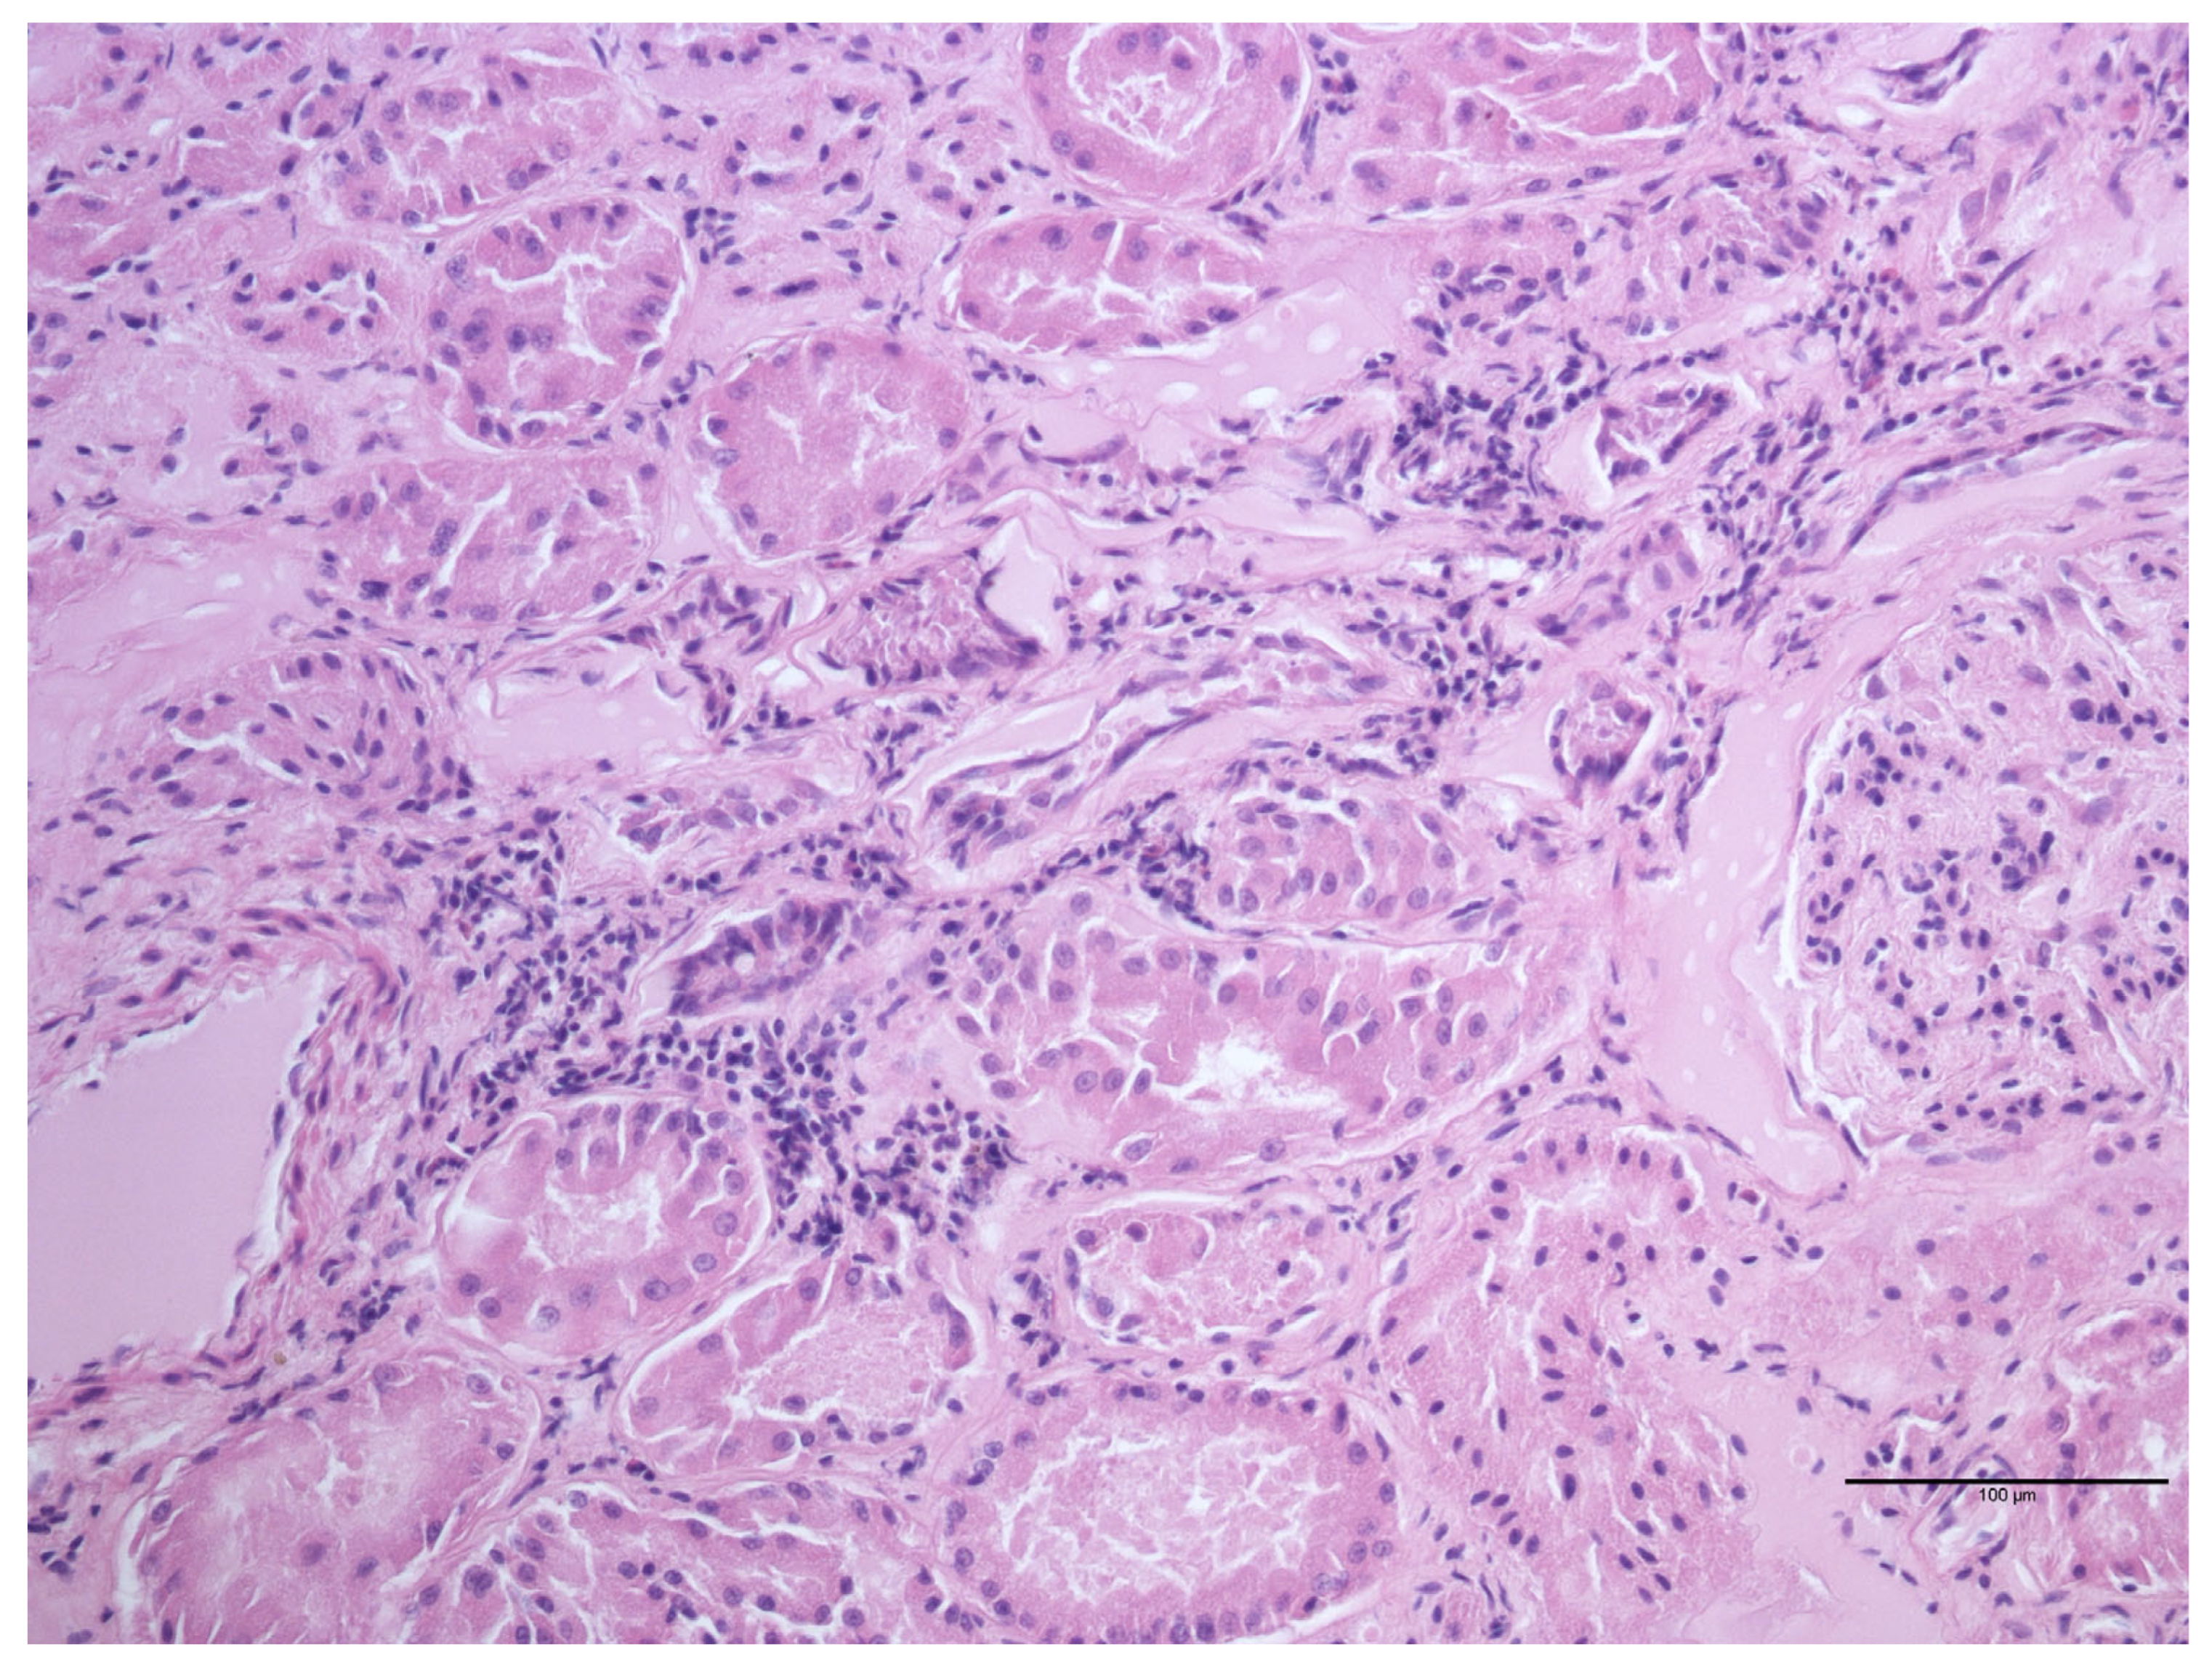

| Lesion | Number of Samples Positive for the Lesion/Total Number of Microscopical Lesions (%) |

|---|---|

| Periportal lymphoid tissue activation | 8/18 (44.4%) |

| Parenchymal lymphocytic infiltrate | 7/18 (38.9%) |

| Perivascular lymphocytic infiltrate | 3/18 (16.7%) |

| Macrophage infiltration | 1/18 (5.6%) |

| Multifocal granuloma | 1/18 (5.6%) |